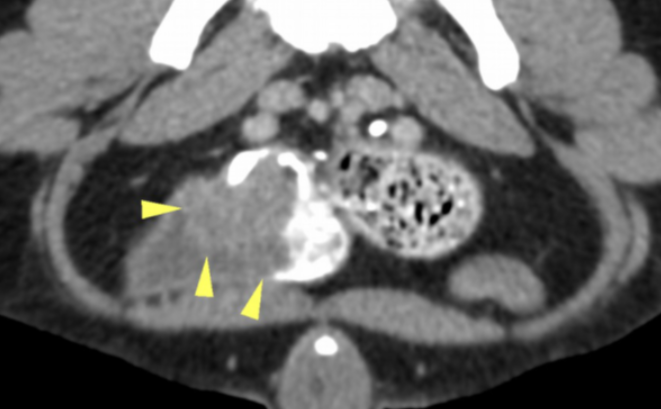

There was an approximately 4cm soft tissue mass located in the bladder trigone (Images 1 – 2). The mass dislocated the right ureter abaxially and dorsally, but was not causing obstruction. There was a large, approximately 7cm x 7cm x2cm parietal mass in the cranial wall of the gastric fundus. The mass protruded into the gastric lumen and was accompanied by an alteration of gastric wall layering (Image 3). A smaller mass was identified in the wall of the greater curvature of the stomach, measuring approximately 4cm x 1cm. The cranial abdominal lymph nodes were enlarged and hypoattenuating (Image 4). No other abnormalities were seen.

Image 1: Axial slice of a post-contrast scan showing the mass in the bladder trigone (arrowheads).